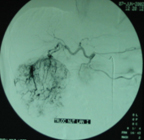

Điện quang can thiệp là tất cả các thủ thuật không phải phẫu thuật với mục đích chẩn đoán hay điều trị qua đường nội mạch hoặc qua da. Điện quang can thiệp đã thay thế nhiều cho phẫu thuật trước đây như phình mạch não ở động mạch thân nền, thông động - tĩnh mạch cảnh xoang hang, thông động - tĩnh mạch mắt. Mục đích thứ nhất của kỹ thuật này là tái lập dòng chảy động mạch hay tĩnh mạch. Nong mạch bằng bóng Balon, bằng laser hay tái thông mạch bằng dụng cụ cơ học, đặt giá đỡ lòng mạch như Stent, làm tiêu cục máu đông trong lòng mạch. Nong mạch được thực hiện cho các mạch máu từ ngoại vi (mạch chi), động mạch tạng (động mạch thận, động mạch mạc treo ..) đến mạch não trong sọ. Mục đích thứ hai của can thiệp nội mạch là làm ngừng dòng chảy động mạch hay tĩnh mạch. Kỹ thuật nút mạch điều trị được sử dụng nhiều nhất trong can thiệp thần kinh như nút mạch trước mổ u màng não, nút mạch các u cuộn cảnh, u cột sống, điều trị chảy máu mũi do u xơ vòm mũi họng, u xơ tử cung. Điều trị thông động - tĩnh mạch cảnh xoang hang. Nút mạch có thể là phương pháp điều trị tiền phẫu hay phối hợp với Gamma knife. Ngày nay với các vật liệu nút mạch mới như Onyx thì tỷ lệ nút khỏi hoàn toàn tăng cao hơn. Nút mạch có thể là phương pháp điều trị tiền phẫu hay phối hợp với xạ trị định vị nổi.

Trước nút khối dị dạng mạch từ động mạch cảnh ngoài

Sau nút khối dị dạng mạch từ động mạch cảnh ngoài